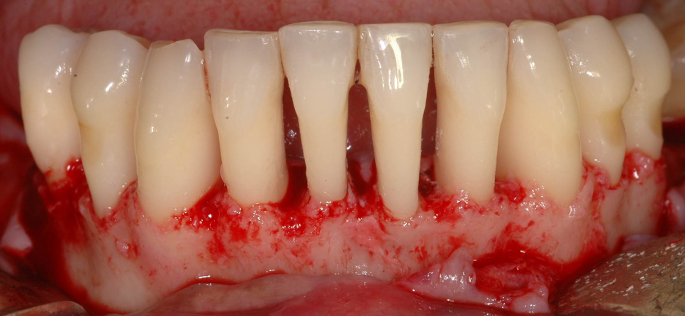

Fotos dos casos clínicos